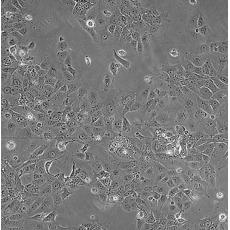

產品名稱 HCC827

中文名稱 人非小細胞肺癌細胞

組織來源 肺腺癌;女性

生長特性 adherent

培養基 RPMI-1640+10% FBS+1% P/S

形態特征 epithelial

細胞描述 This lung adenocarcinoma has an acquired mutation in the EGFR tyrosine kinase domain(E746-A750 deletion).